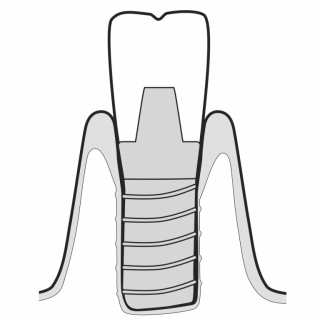

MAINTAIN IMPLANTS

GBT steps deliver a minimally invasive method to protect implant surfaces. 04 AIRFLOW® and 05 PERIOFLOW® with PLUS Powder are gentle on implant surfaces, while metal instruments may scratch.

TREAT MUCOSITIS

While gentle on peri-implant tissues, AIRFLOW® with PLUS Powder safely reaches and cleans any ruggedness on implant surfaces for optimum biofilm removal. GBT is the state-of-the-art approach to implant maintenance.

TREAT PERI-IMPLANTITIS

PERIOFLOW® with PLUS Powder removes subgingival biofilm with unequalled limitation of peri-implant bleeding.The PIEZON® PI Instrument removes the remaining abutment calculus thereby preserving the implant surface.